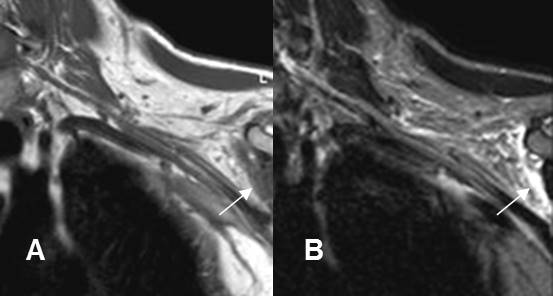

Fig 143. Neuropraxia.

A: RM coronal en T1y B: RM coronal en STIR. Cambios inflamatorios por encima de los vasos subclavios, que rodean las raíces nerviosas, las cuales permanecen integras. La lesión se produjo después de una luxación de hombro.